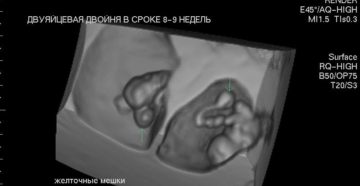

Беременность двойней — особенности беременности и родов Многоплодная беременность – серьезная нагрузка для женского организма….